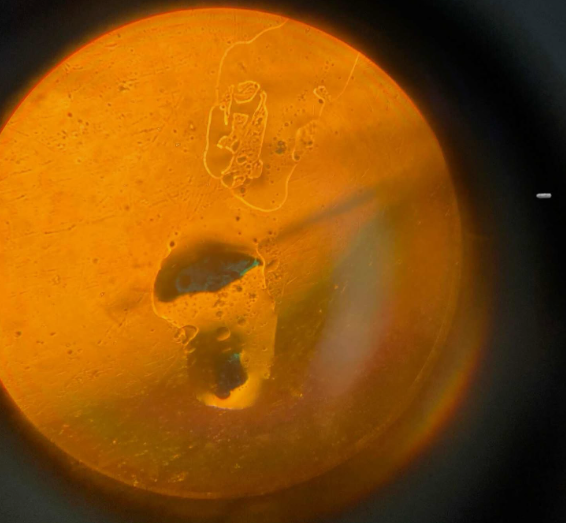

HOOK WORM FILARIFORM W.M

ANCYLOSTOMA CANINUM OVA W.M

DIPYLIDIUM CANINUM OVA

ERYTHOMA PANCREATICUM OVA W.M

FACIOLA HEPATICA

TRICHURIS TRICHIURA OVE WM

HYEMENELOPIS DIMINUTA OVA W.M

TAENIA SAGINATA

ASCARIS LUMBRICOIDES OVE WM

STRONGYLOIDES FILARIFORM WM